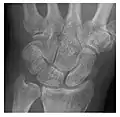

High-energy trauma fractures

Occult osseous injuries may result from a direct blow to the bone by compressive forces of adjacent bones against one another or by traction forces during an avulsion injury. Lesions in the tibial plateau, hip, ankle, and wrist are often missed. In a tibial plateau fracture, any disruption of the posterior and anterior cortical rims of the plateau should be sought. Impaction of subchondral bone will appear as an increased sclerosis of the subchondral bone (Figure 1). In the hip, posterior acetabular fractures also present subtle radiographic findings. The acetabular lines should then be carefully examined keeping in mind that the posterior rim, which is harder to see on X-rays, is more frequently fractured than the anterior rim (Figure 2). In the wrist, detection of carpal bone fractures is often challenging, with up to 18% of scaphoid fractures radiographically occult. Carpal fractures, especially the scaphoid, are associated with the risk of avascular necrosis. In apparently normal wrist radiographs from symptomatic patients, if there is history of a fall on an outstretched hand with pain in the anatomic snuffbox, suggesting scaphoid injury, the initial examination with posteroanterior, lateral, and pronation oblique views must be complemented by other specific views such as supination oblique and the "scaphoid" view A careful examination of cortices for evidence of discontinuity or offset and cancellous bone for lucency is necessary (Figure 3).[1]

c

Figure 3: A 26-year-old man presenting with wrist pain after being assaulted. (a) Initial anteroposterior radiograph shows a subtle linear lucency within the scaphoid extending to the scaphocapitate articular surface that was overlooked (arrow). (b) Initial "scaphoid" view was negative. (c) Followup anteroposterior radiographs, 12 days later, shows obvious scaphoid fracture (arrows).[1]